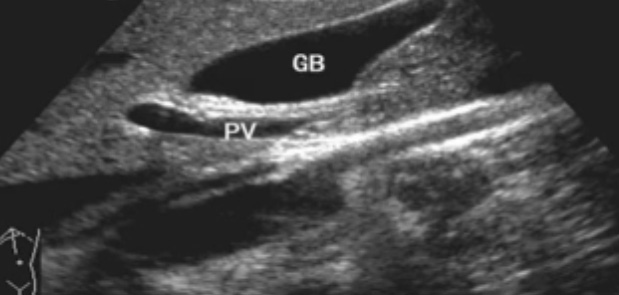

一、正常膽囊超聲圖像有的時(shí)候經(jīng)常發(fā)現(xiàn)檢查不到膽囊,其實(shí)有幾種可能性,檢查人員的技術(shù)不過(guò)關(guān)沒發(fā)現(xiàn)膽囊,就要找上級(jí)醫(yī)生會(huì)診,如果還是沒找到的話就不是技術(shù)問(wèn)題。結(jié)石或腫瘤充滿膽囊,使其液腔消失,慢性膽囊炎使得膽囊萎縮或膽囊壁肥厚而囊腔消失患者已進(jìn)食,膽囊處于膽汁排空的狀態(tài),膽囊先天性過(guò)小或缺失;膽囊位置極端異常(可能很低或位于左側(cè))膽囊切除術(shù)后(注意詢問(wèn)病史)。